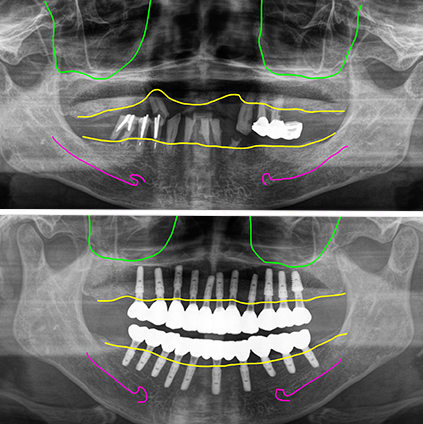

결국 살릴만한 치아가 전혀 없어서 모두 발치를 결정하고 전체임플란트를 계획했습니다. 다행이 뼈상태는 양호하신 편이라 즉시하중을 시도하기로 했습니다.

위11개, 아래10개즉시 식립

수술은 위아래 동시에 진행했습니다. 비교적 뼈상태가 좋아서 뼈이식은 따로 하지 않았습니다.

위에는 11개, 아래는10개의 임플란트를 발치와 동시에 즉시 식립했으며 위에는모두, 아래는 8개의 임플란트에 지대주를 연결해서 임시치아를 제작해 세팅했습니다.

수술 후 4개월에 최종보철을 만들기 위한 스캔바디 스캔을 한 후 최종보철을 만들어 끼웠습니다. 즉시하중 임시치아를 적용했지만 모든 임플란트는 골융합이 잘 되었습니다.